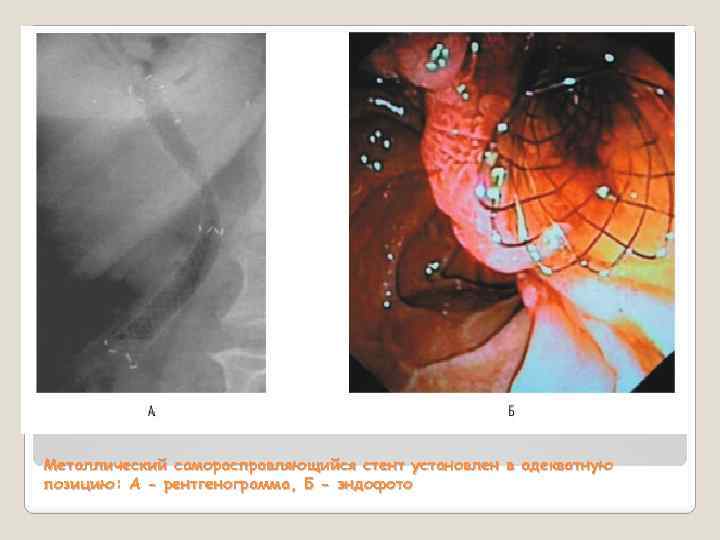

Металлический саморасправляющийся стент установлен в адекватную позицию: А - рентгенограмма, Б - эндофото